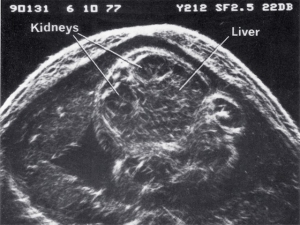

- Fetal anatomy

| 1968 | Demonstration of fetal orbits, heart, bladder, kidneys and scrotum |

| 1970 | Introduction of grey scale ultrasound, improving dramatically the demonstration of normal and abnormal structures in the fetus, placenta and mother |

| 1980 | Demonstration of fetal lung, liver and bowel maturation by grey scale ultrasound |